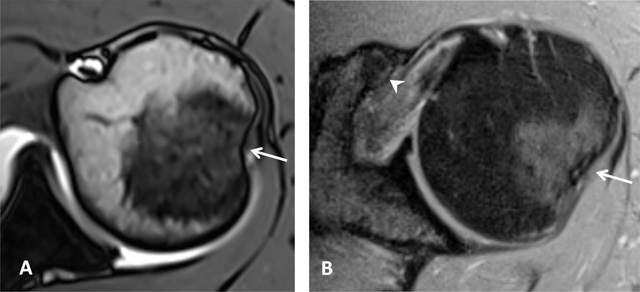

Figure 3

Subchondral cysts of the humeral head and normal bare area. (A) Axial and (B) Coronal oblique fat-suppressed T1-weighted MR arthrographic images show subchondral cysts at the attachment of the infraspinatus tendon (arrow). Coronal oblique section of the same patient discloses a normal bare area in the posterolateral aspect of the humeral head with small fibrocystic changes that communicate with the joint and should not be mistaken for a cartilage defect (arrow, B). Such changes are common and often asymptomatic.

Figure 4

Normal humeral head versus Hill-Sachs lesion. (A) On the axial T2 gradient echo weighted MR image, there is a slight flattening of the posteroinferior surface of the humeral head (arrow), which is a normal finding. (B) Axial fat saturated T2-weighted MR image obtained at the level of the coracoid process (arrowhead, B) typically shows a Hill-Sachs defect (arrow) in a patient with history of anterior shoulder dislocation.